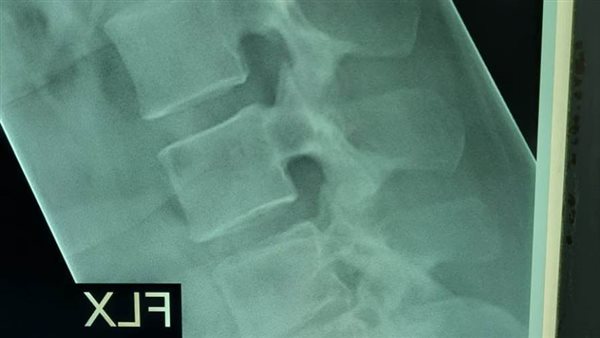

استحدث مستشفى المنيرة العام، خدمات طبية وجراحات جديدة، ولأول مرة أجريت فيه جراحة عمود فقرى، لمريضة تعاني من آلام مزمنة أسفل الظهر، ومنذ 3 أشهر زادت بطريقة شديدة، وتم فحص المريضة وعمل الأشعات اللازمة للتشخيص، وتشخصت بأنها حالة انزلاق فقارى قطني، بين الفقرات القطنية الرابعة والخامسة، والأولى العجزية، وهناك ضاغط علي جذور الأعصاب.

وعلى الفور تم استخراج قرار علاج علي نفقة الدولة، وإجراء جراحة توسيع للقناة العصبية، ومخارج جذور الأعصاب، وتثبيت للفقرات بواسطة أعمدة ومسامير، ودمج للفقرات بواسطة رقعة عظمية ذاتية، وقفص كربوني بين الفقرات القطنية الرابعة والخامسة، واستمرت الجراحة 3 ساعات.